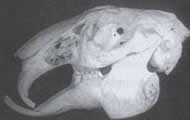

En

esta imagen podemos ver un cráneo de conejo con la

dentadura normal. Claramente se ve como los incisivos

superiores pasan por delante de los inferiores. Y de

esta forma el conejo puede cortar las hierbas que come.

El hueso de la mandíbula, es prácticamente horizontal si

lo apoyáramos al cráneo en una superficie lisa. |